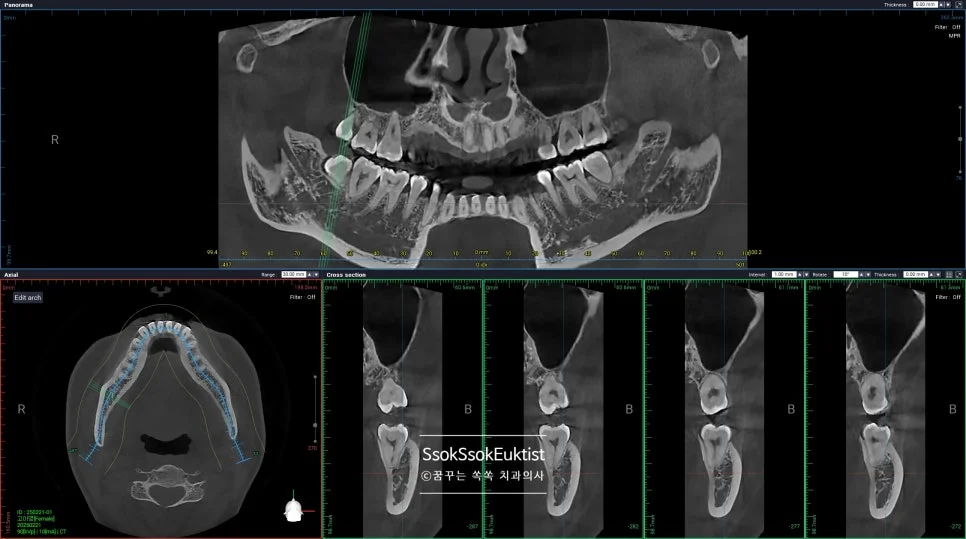

CBCT(3D CT)로 신경관 위치 확인

CBCT 우측 하악 매복 사랑니 신경관 근접도 분석

우측 CBCT — 신경관 근접도 분석

CBCT 좌측 하악 매복 사랑니 신경관 근접도 분석

좌측 CBCT — 신경관 근접도 분석

매복된 사랑니는, CT를 통해 신경관과 맞닿아 있진 않은지 정밀하게 분석 후 발치를 시도합니다.